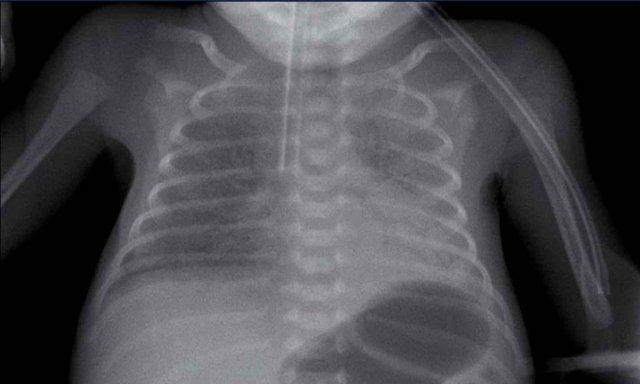

29 tuần + 1, ngày đầu tiên. CPAP.

Nhìn vào hình ảnh lần đầu.

Những phát hiện là gì?

Findings:

- Reticulogranular opacification

of lungs - Air bronchogram

- Consolidation in the right lower lobe

- Heart, vessels and

diaphragm are poorly defined. - Đặt sai vị trí catheter tĩnh mạch rốn (mũi tên), có thể nằm trong tĩnh mạch phổi.

- Nasogastric tube (NG tube) in good position.

Đây là trường hợp nặng của hội chứng suy hô hấp (RDS).

Chẩn đoán phân biệt bao gồm nhiễm trùng phổi do tình trạng đông đặc không đối xứng.